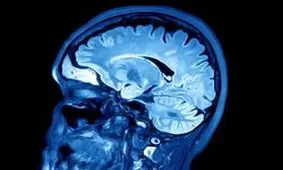

هر ساله در تاریخ ۲۱ سپتامبر "روز جهانی آلزایمر" گرامی داشته میشود.

محققان روش جدیدی ابداع کردهاند که از تستهای موسیقی برای بررسی فعالیت مغز با هدف تشخیص زوال عقلی در سنین بالا استفاده …

پژوهشگران با توجه به نتیجه یک مطالعه که تفاوتهای مشخصی را در الگوهای فعالیت افراد مسن مبتلا به آلزایمر در بعدازظهرها…